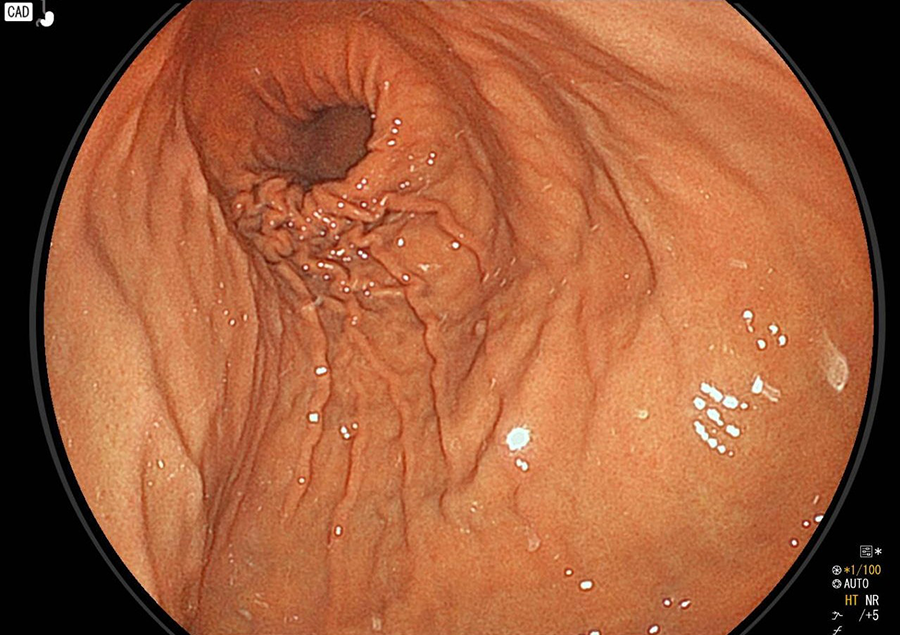

鳥肌胃炎

ピロリ菌に感染すると、まず胃の出口付近から炎症が始まり、胃全体に広がっていきます。これは胃の出口付近(前庭部)にピロリ菌に対する免疫反応によってリンパ球がたくさん集まり、このようにブツブツした粘膜になります。これを「鳥肌胃炎」とよび、スキルス胃がん発生のリスクが高いといわれます。